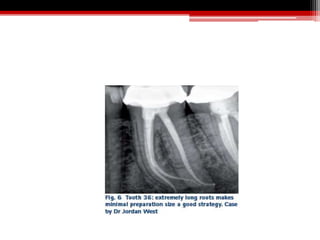

 Recently, maintaining structural integrity of the peri-cervical area of the tooth

(about four mm above and below the alveolar crest) has been emphasised.

 Maintenance of the peri-cervical dentin (PCD), especially in molars is felt to be

critical to their long-term survivability and optimum function.